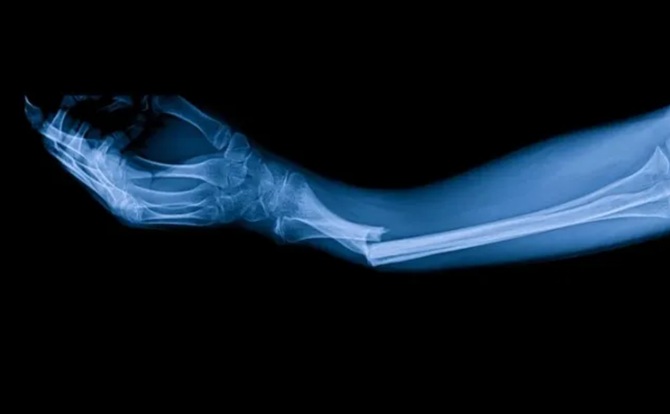

Chinesische Wissenschaftler ließen sich von der Fähigkeit von Austern inspirieren, dank ihres natürlichen Bioklebstoffs fest an nassen und beweglichen Oberflächen zu haften. Nach diesem Prinzip konnten sie Bone-02 entwickeln. In einem Experiment erhielt ein Patient mit einer Handgelenksfraktur eine Injektion durch einen kleinen, nur 3 cm langen Einschnitt. Innerhalb von drei Minuten war der Knochen verheilt, während bei einer Standardoperation eine Metallstruktur eingesetzt und anschließend erneut entfernt werden musste. Drei Monate nach dem Eingriff war der Knochen vollständig und ohne Komplikationen verheilt. Dies ist nur eine der vielen erfolgreichen Anwendungen von Bone-02.